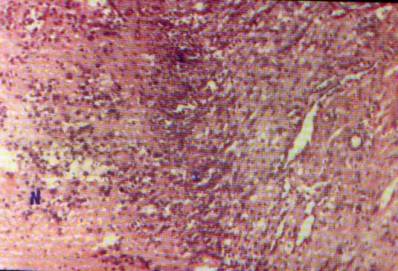

En síntesis, del estudio de los elementos celulares presentes se

evidencia un fenómeno inmune activo, bien estructurado y desarrollado,

orientado principalmente a la inmunidad "T", con asociación adecuada

de elementos "B" y una alta eficiencia necrotizante en el seno del

tumor; dada por la evidente desproporción entre elementos celulares linfoides y

necrosis efectiva, comparada con otros casos de tumores malignos sin

tratamiento. Observándose en

nuestro caso un elevado porcentaje de necrosis (80%) con moderada presencia de

elementos linfoides (escasos pero eficientes), contrastando con casos en que la

reacción peritumoral es nula, con presencia de fibrosis únicamente (que sirve

de substrato al crecimiento tumoral). 0 con activa afluencia de

polirnorfonucleares, esonófilos, linfocitos y plasmocitos desordenados y en

grandes cantidades pero ineficientes para detener el crecimiento tumoral (cita

38).